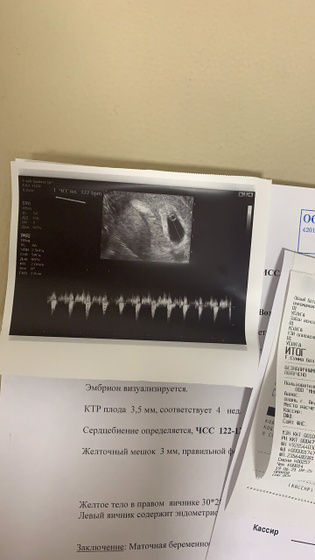

Девочки, сегодня ходила опять на узи, сердечко бьется 122-125(брадикардия) вчера было 95 уд/мин) это конечно вселило надежду) что думаете по этому поводу? У кого так было?) Замрет или нормально будет? Как думаете?

Говорят, может и замереть, на таком сроке должен быть 140-160) не знаю что и думать?